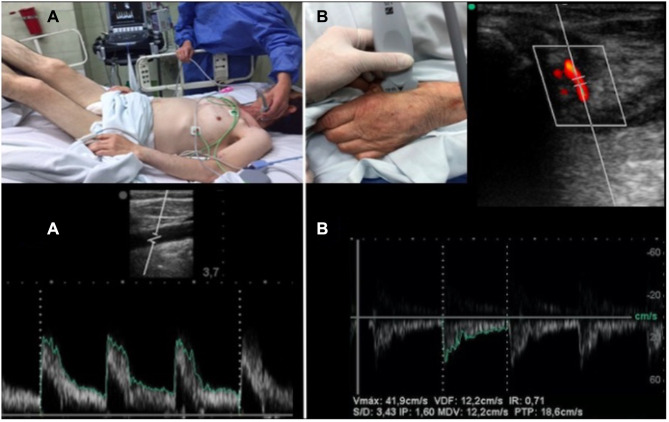

Objective: To determine if there is a difference in in-hospital mortality, fluid balances, norepinephrine initiation and recovery time of blood pressure, when comparing the resuscitation of the patient who is admitted to the emergency room in septic shock by applying the ultrasound protocol (USER) versus the standard of care.

Patients and methods: This is a prospective, cohort study conducted in the emergency room of a highly complex hospital of patients with septic shock.